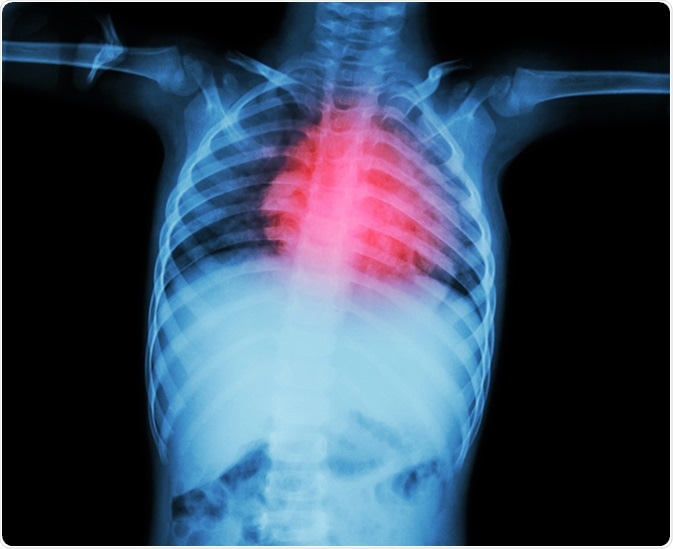

Rheumatic heart disease. Image Credit: Puwadol Jaturawutthichai / Shutterstock